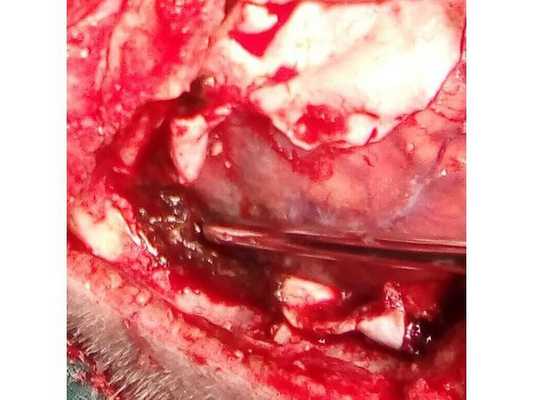

Пациент взят на операцию: ⠀•⠀Выполнен дугообразный разрез мягких тканей в правой лобно-височно-теменной области. Скелетирована кость. ⠀•⠀Наложены два фрезевых отверстия, из которых краниотомом выпилен костный лоскут 6,0*8,0 см. ⠀•⠀Произведён гемостаз моно- и биполярной коагуляцией, воском по ходу доступа. ⠀•⠀Твёрдая мозговая оболочка вскрыта подковообразно. Визуализирована субдуральная гематома, представленная плотными сгустками тёмно-вишнёвого цвета (рис. 3). ⠀•⠀Начато удаление сгустков путём аспирации и отмыванием физиологическим раствором. Общий объём субдуральной гематомы около 120 мл. Признаков черепно-мозговой травмы (кортикальных очагов ушиба, травматического субарахноидального кровоизлияния, гиперемии, отёка головного мозга) нет. ⠀•⠀При удалении сгустков с конвекситальной поверхности лобной доли открылось интенсивное венозное кровотечение. С целью доступа к источнику кровотечения разрез мягких тканей продолжен в конвекситальном направлении и краниотомом выпилены два дополнительных костных лоскута (из-за интенсивности кровотечения найти локализацию источника было затруднительно). ⠀•⠀Визуализировано кровоточащее образование, сращённое с твёрдой мозговой оболочкой и корой головного мозга, по виду — сосудистая мальформация (рис. 4). ⠀•⠀Гемостаз подходящих сосудов и самого образования выполнен последовательной биполярной коагуляцией (рис. 5: сосудистая мальформация указана наконечником аспиратора). ⠀•⠀Кровотечение остановлено. Мозг расправился, пульсирует. Твёрдая мозговая оболочка ушита викрилом с одновременным подшиванием по периметру трепанационного окна (рис. 6). ⠀•⠀Дефекты твёрдой мозговой оболочки и сосудистая мальформация укрыты гемостатической губкой (рис. 7). ⠀•⠀Костные лоскуты уложены на место (рис. 8). ⠀•⠀Послойный шов раны выполнен викрилом и капроном. ⠀•⠀Кожа ушита обвивным швом по Мультановскому. Ретроспективно на фронтальной ангиограмме можно заподозрить сосудистую мальформацию, ставшую источником гематомы (рис. 9). На девятые сутки после операции для обеспечения проходимости дыхательных путей, проведения длительной искусственной вентиляции лёгких, облегчения санации трахеи и бронхов пациенту выполнена нижняя трахеостомия по Бьёрку.